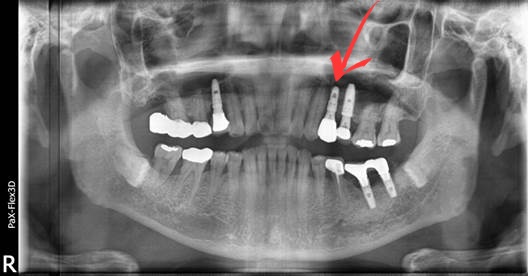

앞서 말씀드린 SCRP 방식으로 치료를 마친 모습입니다.

(후) 2022-01-18

추가로 설명해 드린다면, 이 환자분은 아스피린을 복용 중이셨는데요.

아스피린은 피를 맑게 하는 항혈전제이기 때문에 수술 후 지혈을 어렵게 합니다.

그러므로 안정적인 임플란트 시술을 위해선 일주일간 조절이 꼭 필요합니다.

그렇다고 환자분이 복용 중인 약을 임의로 중단하는 것은 위험할 수 있습니다.

따라서 수술 부위와 깊이, 예상 출혈량에 대해 담당 치과 선생님과 충분히 상의한 후 항혈전제를 처방한 주치의와 최종 상의해서 약물 중단 여부를 결정해야 합니다.

이는 아스피린뿐만 아니라, 다른 약물들도 치료와 예후에 영향을 줄 수 있으므로 담당 의사에게 복용 중인 약물, 기저질환 등을 정확하게 알리셔야 합니다.